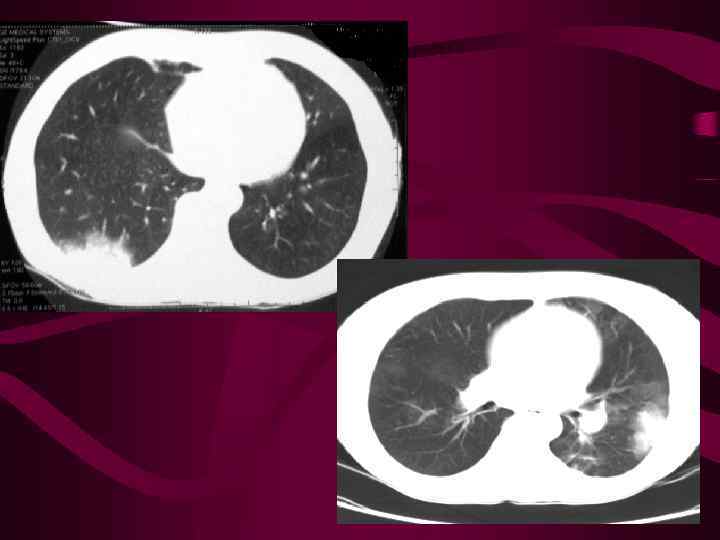

Хроническая ТЭЛА. Воздушность в нижней доле слева повышена, сосудистый рисунок обеднен. Справа картина альвеолярного отека.

Хроническая ТЭЛА. Воздушность в нижней доле слева повышена, сосудистый рисунок обеднен. Справа картина альвеолярного отека.